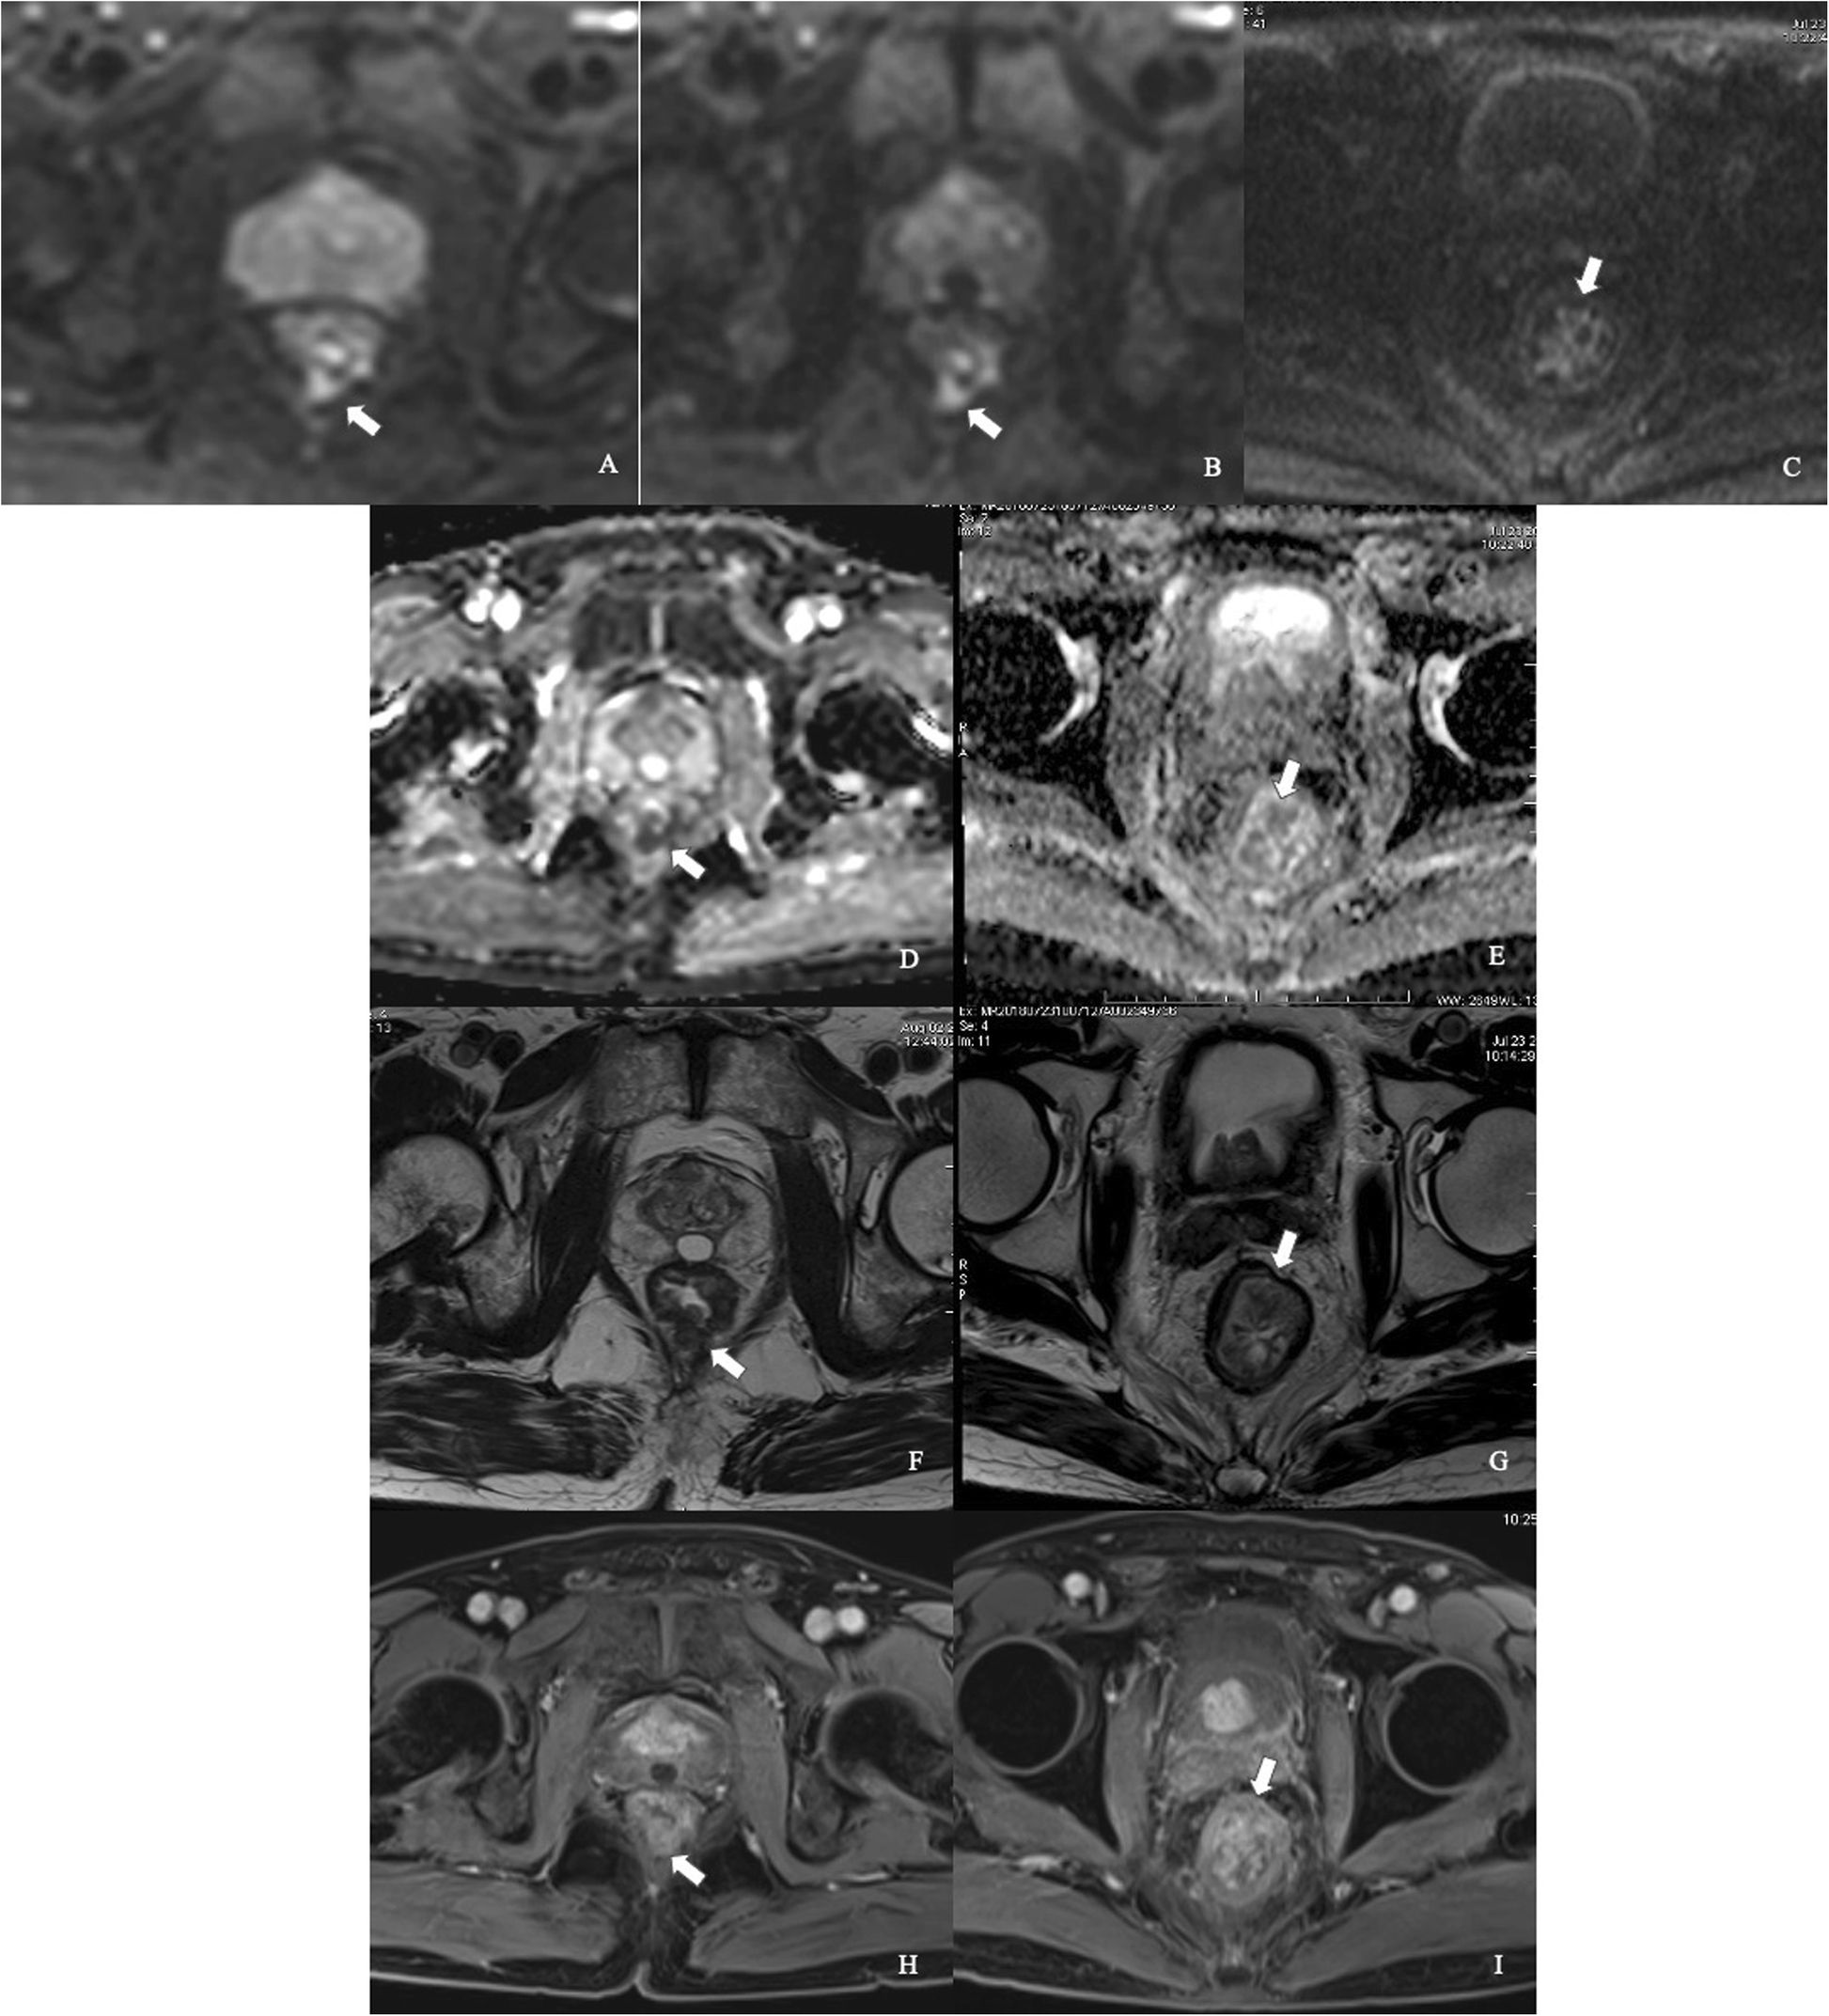

Fig. 4

Comparison between iShim- and SS-EPI-DWI in patients after CRT. iShim-DWI of b = 800 s/mm2 (a) and b = 1600 s/mm2 (b) showed higher SNR and CNR with lower signal noise compared with SS-EPI-DWI of b = 1000 s/mm2 (c). ADC map (e) of iShim-DWI showed better image quality compared with ADC map (f) of SS-EPI-DWI. T2W images (f and g) and dynamic T1W images (h and i) showed the same location of lesion (arrows) for iShim- and SS-EPI-DWI cohort, respectively